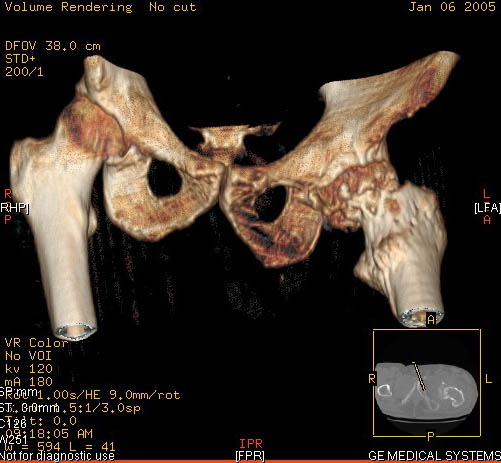

И снова вопрос по эндопротезированию: Пациенту 51 год. Болен с 2000 г, когда отметил умеренные, нараостающие боли в в/3 левого бедра, прогрессирующую контрактуру лев Т/Б сустава.

05.12.04 после падения на бедро боли резко усилились, нога стала неопорной. На рентгенограмме обнаружен патологический перелом шейки бедренной кости. Обследован в отделении костной онкологии. Результат биопсии: асептический некроз проксимального отдела бедренной кости. Вопрос: выбор технологии эндопротезирования - цементная или бесцементная версия. Заранее благодарю! С уважением,А.В.Владзимирский

Проксимальный отдел бедра не виден достаточно на представленных рентгенограммах; но то, что видно, как раз наводит на мысли о цементной фиксации - цилиндрический канал, измененный calcar, кистозные изменения в области большого вертела и т.д.

Как то очень подозрительно выглядит проксимальный отдел бедра для такого очень простого гистологического заключения. Вы уверены, что гистология настолько благополучна и в каком варианте она выполнялась: пункционная или открытая с забором костного блока? Не уверен на все сто , но область проксимального отдела бедра - одно из излюбленных мест для гигантоклеточной опухоли, которая зачастую озлакочествляется (имел два подобных наблюдения). Из своей практики могу сказать, что, к сожалению, информативность пункционной биопсии не сравнима с открытой техникой. Поэтому прежде чем решать цементный или бесцементный протез использовать, я бы повторил биопсию в сочетании со сканированием скелета, сывороточная щелочная фосфатаза, кальций, фосфор сыворотки, СОЭ, С- реактивный белок,

Soglasen s Евгений И Чекашкин, proximal Femur does not look right. Sarcoma? Pagets, Osteomyelitis?. Technicality of the implantaion will be dependent upon underlying pathology, and the surgeon's level of comfort.

Действительно, проксимальный отдел бедра выглядит подозрительно. По-моему напоминает болезнь Педжета. Кстати, гистологическое заключение в таком случае часто звучит как "хроническое воспаление", "асептический некроз с элементами лейкоцитарной инфильтрации" и т.п. Далеко не все патоморфологи имеют достаточный опыт для дифференцировки костной патологии.